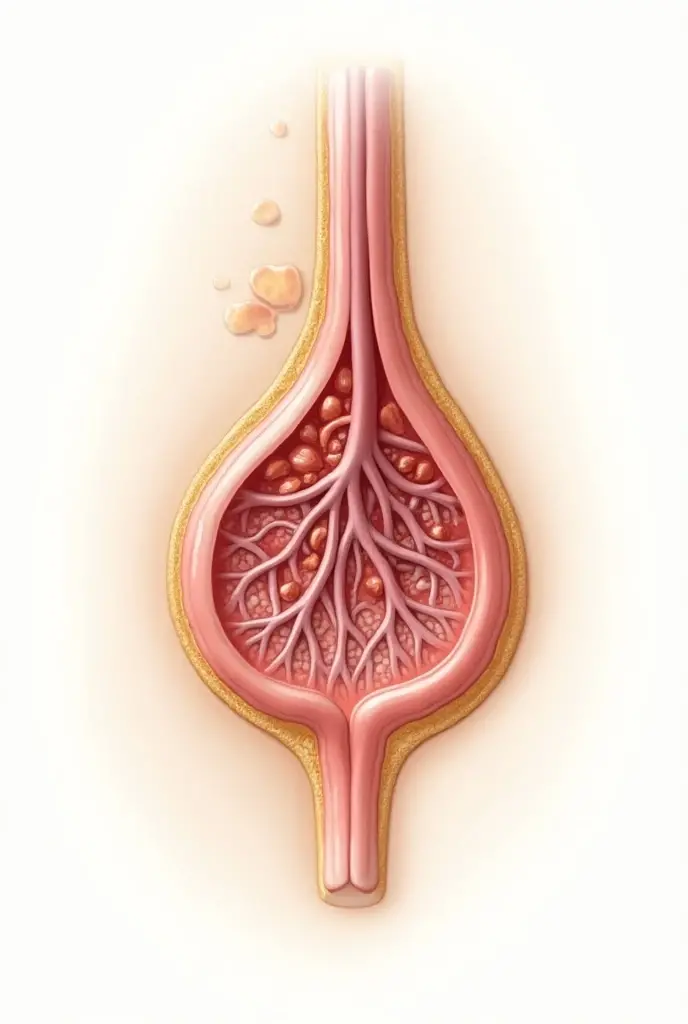

Realice un dibujo de la piel. Coloque las siguientes referencias: Epidermis Fermis Hypodermis Keratinized squamous stratified epithelium Hair Sebaceous gland Sweat gland Pilo erector muscle Connective tissue Blood vessels Nerves Adipocytes

Epidermis Fermis Hypodermis Keratinized squamous stratified epithelium Hair Sebaceous gland Sweat gland Pilo erector muscle Connective tissue Blood vessels Nerves Adipocytes